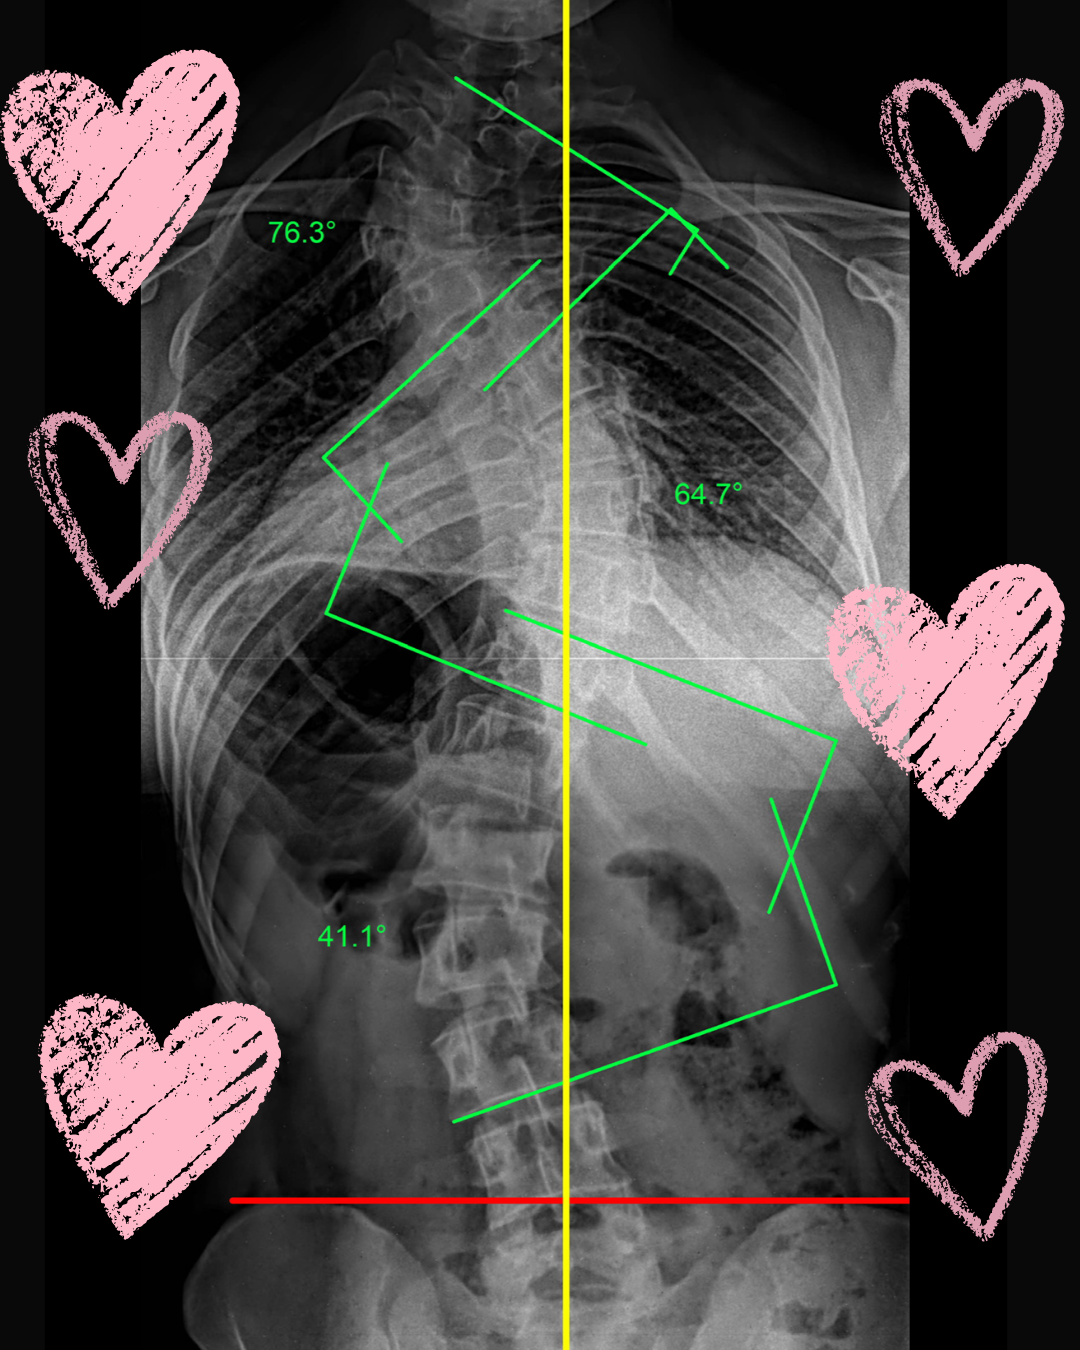

Scoliosis and Self Love: My Honest Valentine’s Day Reflection